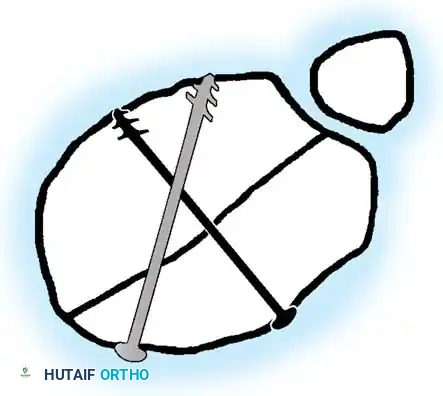

Fig. 33-171: Classification of floating knee injuries in children. (Redrawn from Letts M, Vincent N, Gouw G: The “floating knee” in children, J Bone Joint Surg 68B:442, 1986.)

The "floating knee" describes an ipsilateral fracture of the femur and tibia, creating a flail knee joint. These are high-energy injuries often associated with polytrauma. The Letts classification (Types A through E) categorizes these based on whether the fractures are open or closed, and whether they involve the diaphysis or the metaphysis/epiphysis.